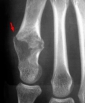

Aspect typique : Lésion lytique métaphysaire ou diaphysaire bien définie avec matrice cartilagineuse.

- tumeur centrée ou excentrée, médullaire, ostéolytique, avec ou sans calcification (arcs, anneaux)

- taille < 3 cm (si > 4 cm évoquer chondrosarcome)

- érosions lobulées du versant endostéal de la corticale osseuse

- pas d'interruption corticale ni de réaction périostée